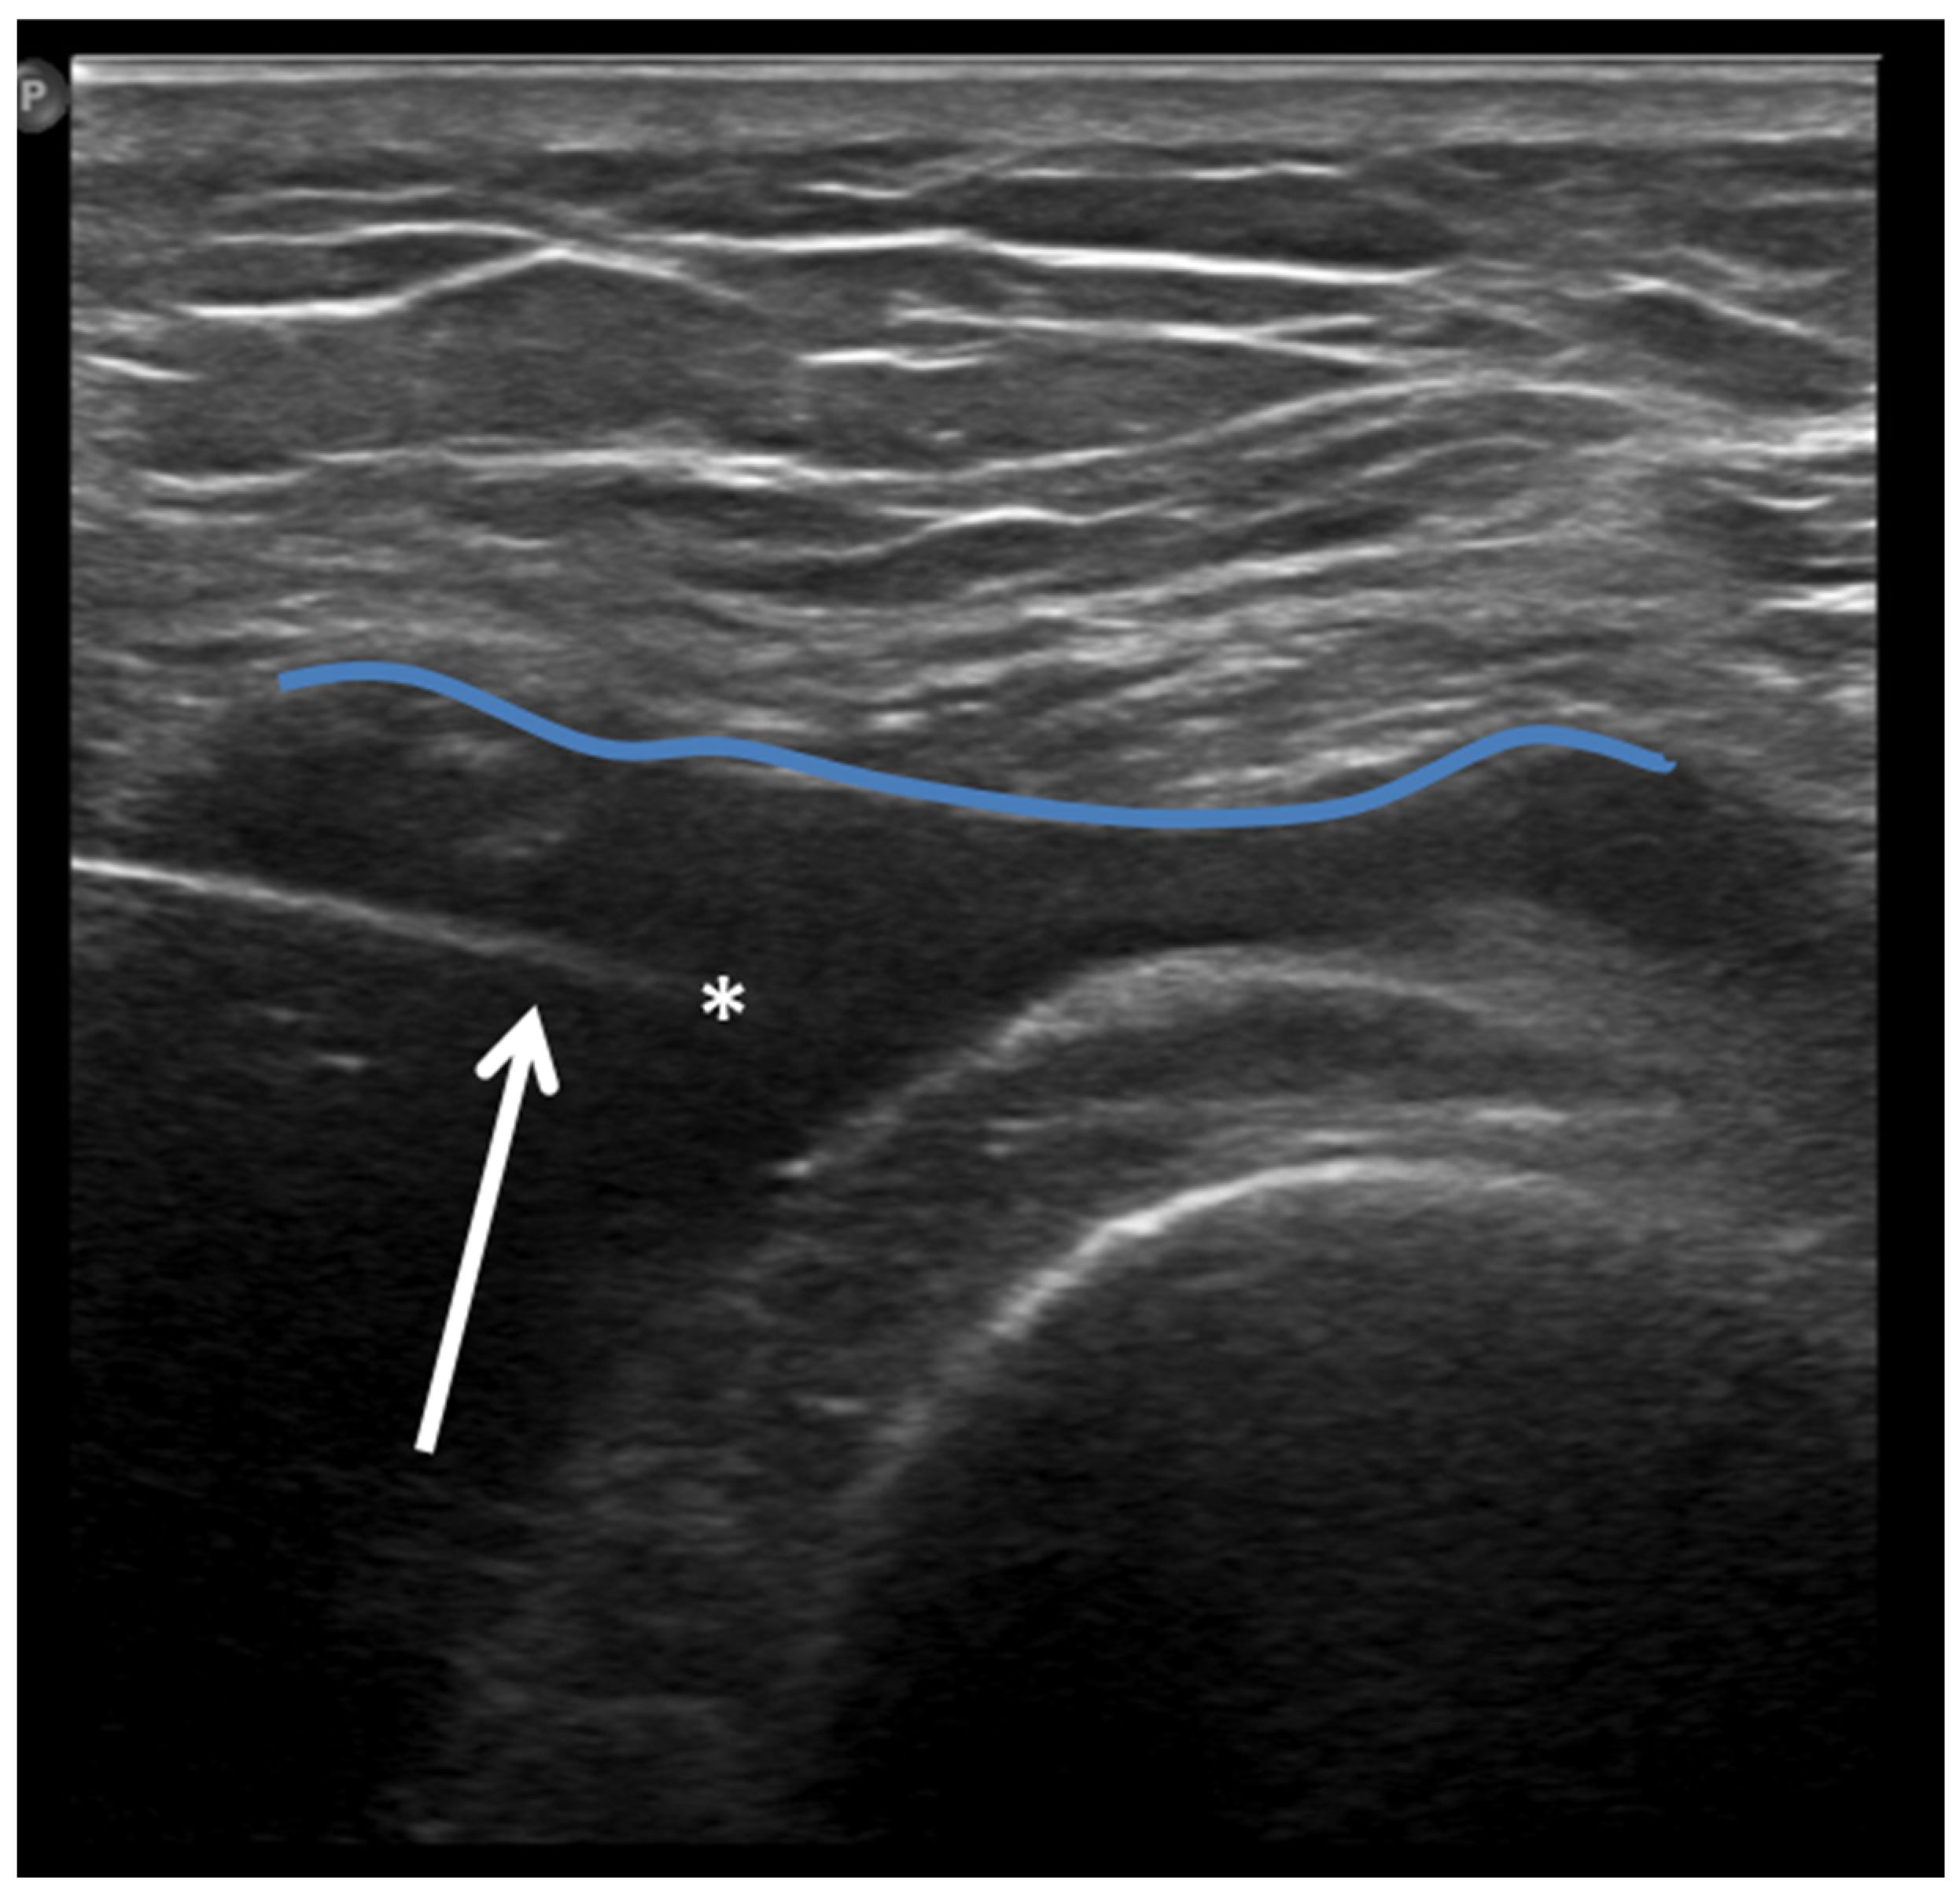

Ultrasound (US) imaging has not traditionally been used as part of the clinical pipeline for OA diagnostics. However, when examining the scientific literature, its role has risen steadily during the last two decades. US assessment of joints offers several advantages, including the ability to assess soft-tissue changes associated with OA and to outline the contour of the bony surface surrounding the joint [64,65]. In addition to detecting structural OA changes, a US can provide insights into inflammatory findings, complementing traditional CR imaging [66]. Several inflammatory findings (e.g., joint effusion/Baker cyst, synovial thickening, and hyper-vascularity), easily detectable throughout a US, are associated with pain exacerbation and disease progression in knee OA (Figure 2, Figure 3 and Figure 4).

Figure 2.

Ultrasound image (B-mode) longitudinal suprapatellar view showing joint effusion (asterisks) and synovial inflammatory thickening (arrow) within the sub-quadricipital recess.